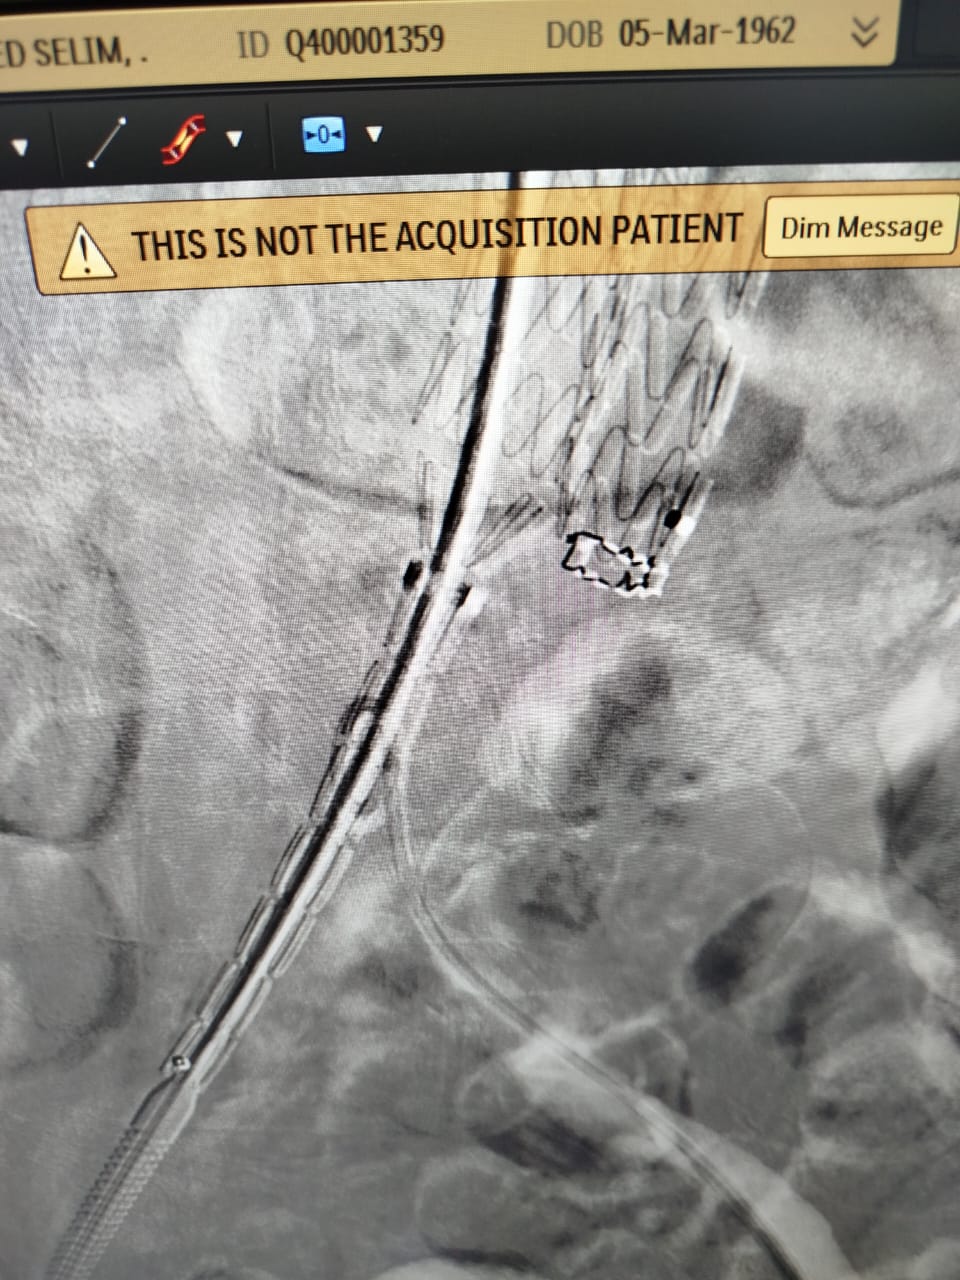

أعلنت الهيئة العامة للرعاية الصحية، عن نجاح أول عملية لعلاج تمدد الشريان الأورطي باستخدام الدعامة المغطاة بتقنية EVAR، لسيدة مسنة، وذلك داخل مستشفى شرم الشيخ الدولى، التابع لهيئة الرعاية الصحية بجنوب سيناء.

وأوضح بيان الهيئة، أن المريضة حضرت إلى مستشفى شرم الشيخ الدولى، وبمناظرة الحالة تم اكتشاف وجود تمدد الشريان الرئيسى للقلب (الشريان الأبهر ) للمريضة، وعليه تم عرض الحالة على قسم جراحة الأوعية الدموية، ووجد أن نسبة حدوث انفجار الشريان لهذه المريضة تتخطى 80%، ووفقًا للبروتوكولات العلاجية أوصى الفريق الطبي المعالج بإجراء عملية لإصلاح تمدد الشريان الأورطي الباطني بتقنية (EVAR) للمريضة.

وأضاف: توفير الكوادر الطبية المؤهلة ليس فقط إنجازًا بل ضرورة استراتيجية لضمان تقديم خدمات صحية ذات مستوى عالمي تليق بالمواطن المصري، مشيرا إلى أن منشآت الهيئة بما في ذلك المستشفيات ومراكز ووحدات صحة الأسرة، تُجهز وفق أعلى المعايير العالمية من حيث الإنشاء والتقنيات الطبية الحديثة، وأوضح أن استخدام تقنيات متطورة مثل تقنية EVAR لعلاج تمدد الشريان الأورطي بدون جراحة، يمثل خطوة نوعية نحو تقليل المخاطر الجراحية وتسريع فترة التعافي، فضلًا عن ضمان العلاج الآمن وفق أحدث الإرشادات الطبية والبروتوكولات العلاجية الدولية.

جدير بالذكر، أن استخدام الدعامة المغطاة EVAR من أحدث العلاجات المتوفرة عالميًا لعلاج تمدد الشريان الأورطي، وقد تم استحداثها ضمن حزم خدمات منظومة التأمين الصحي الشامل الجديدة، حيث توفر عدة مزايا منها استخدام نوع تخدير أبسط ويظل المريض مدة أقل تحت تأثير المخدر، مع عدم الاحتياج لنقل دم، وعدم الاحتياج للبقاء في العناية المركزة، سرعة العودة للمنزل بعد يوم واحد من العملية مقارنه بعشرة أيام علي الأقل في حالة الفتح الجراحي.